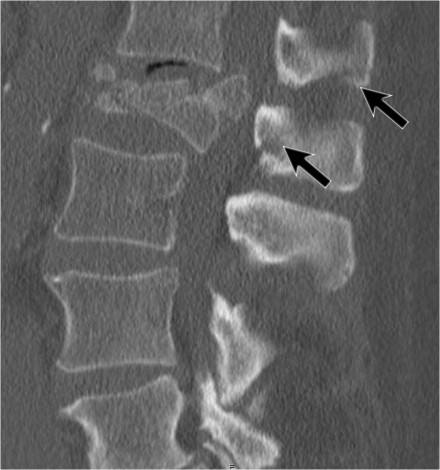

Here another distraction injury.

At surgery the rupture of the supraspinous ligament was confirmed (red and black arrows)